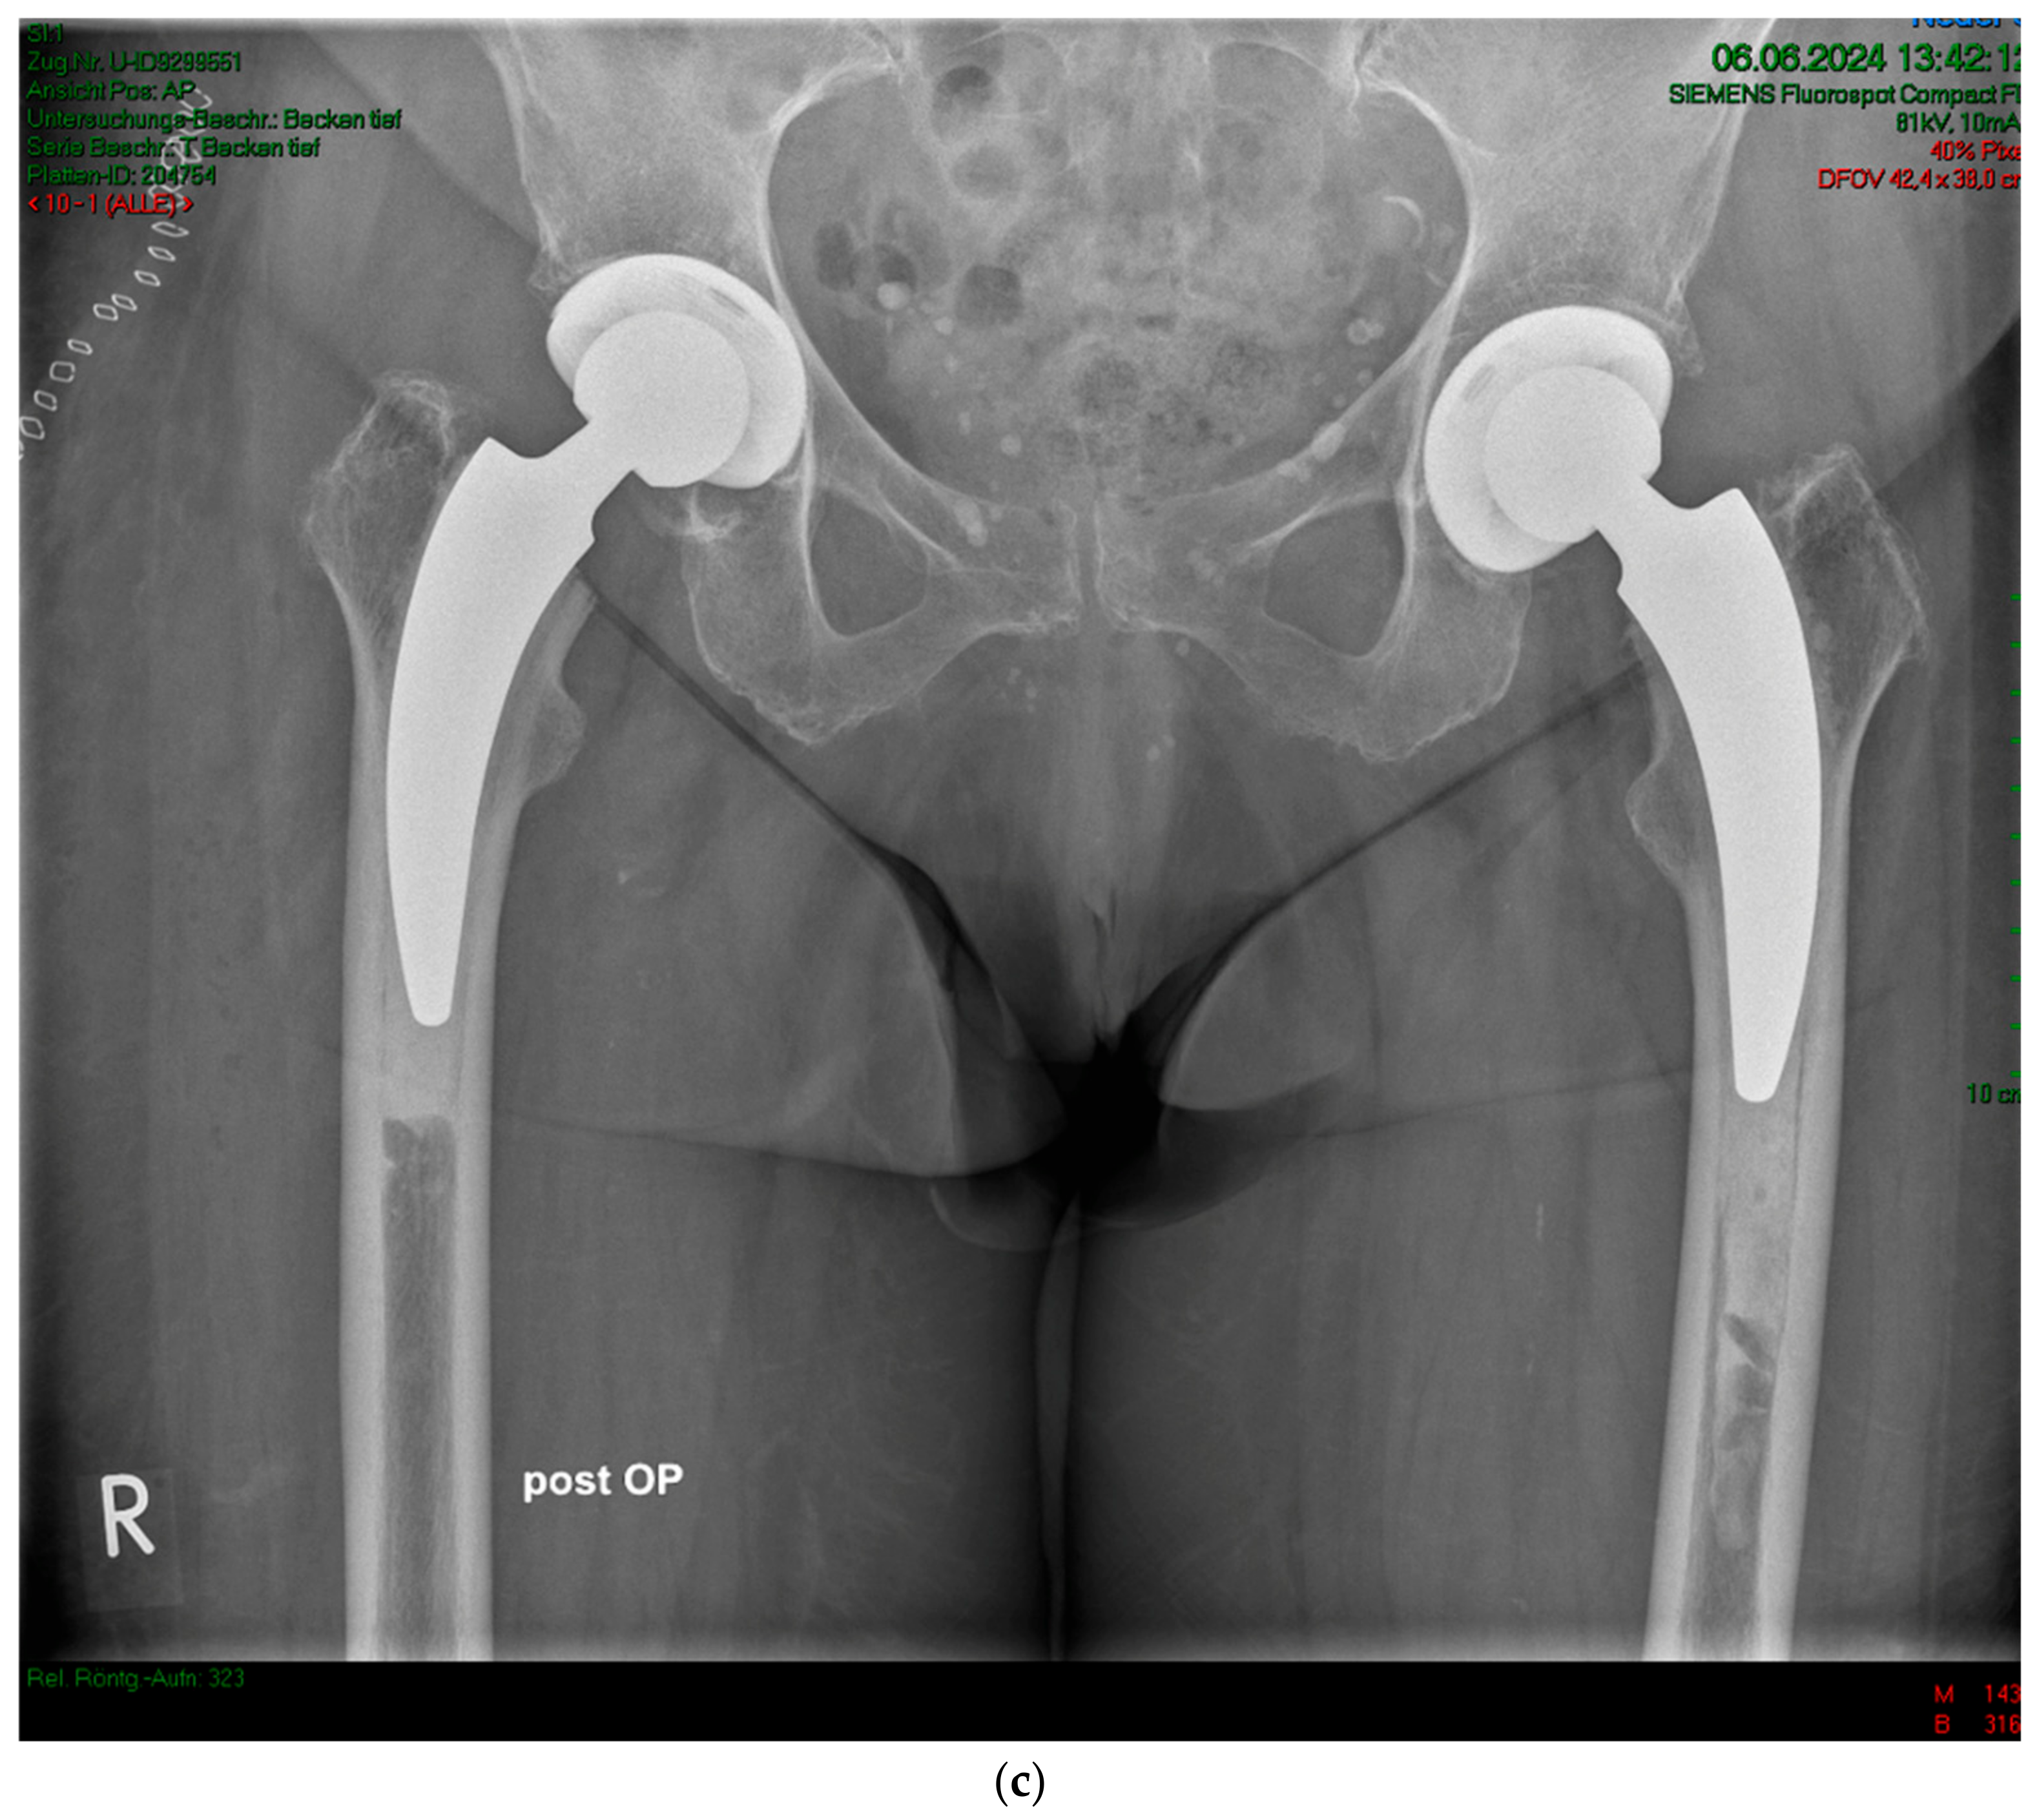

Figure 3.

(a) Case #2: Osteoarthritis, female, 85 years old, bilateral sequential implantation of an A2 stem, Dorr B-C femora. (b) Left side: slight distalization of the cement stopper. (c) Right side: no positional change of the cement stopper during the operation.